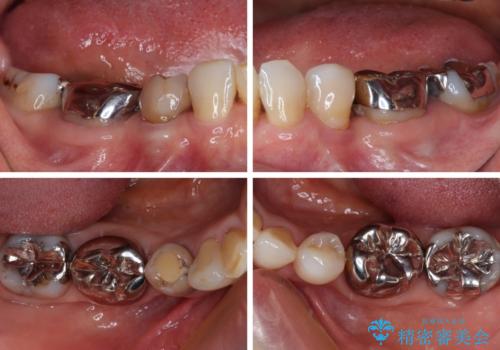

- 奥歯の目立つ銀歯と、神経が失活して変色した前歯を気にして来院された患者様です。

銀歯と歯の間に隙間があり、冷たいものがしみる知覚過敏の症状が認められたため、銀歯を白くするだけでなく、知覚過敏症状の改善も狙って補綴治療を行うこととしました。